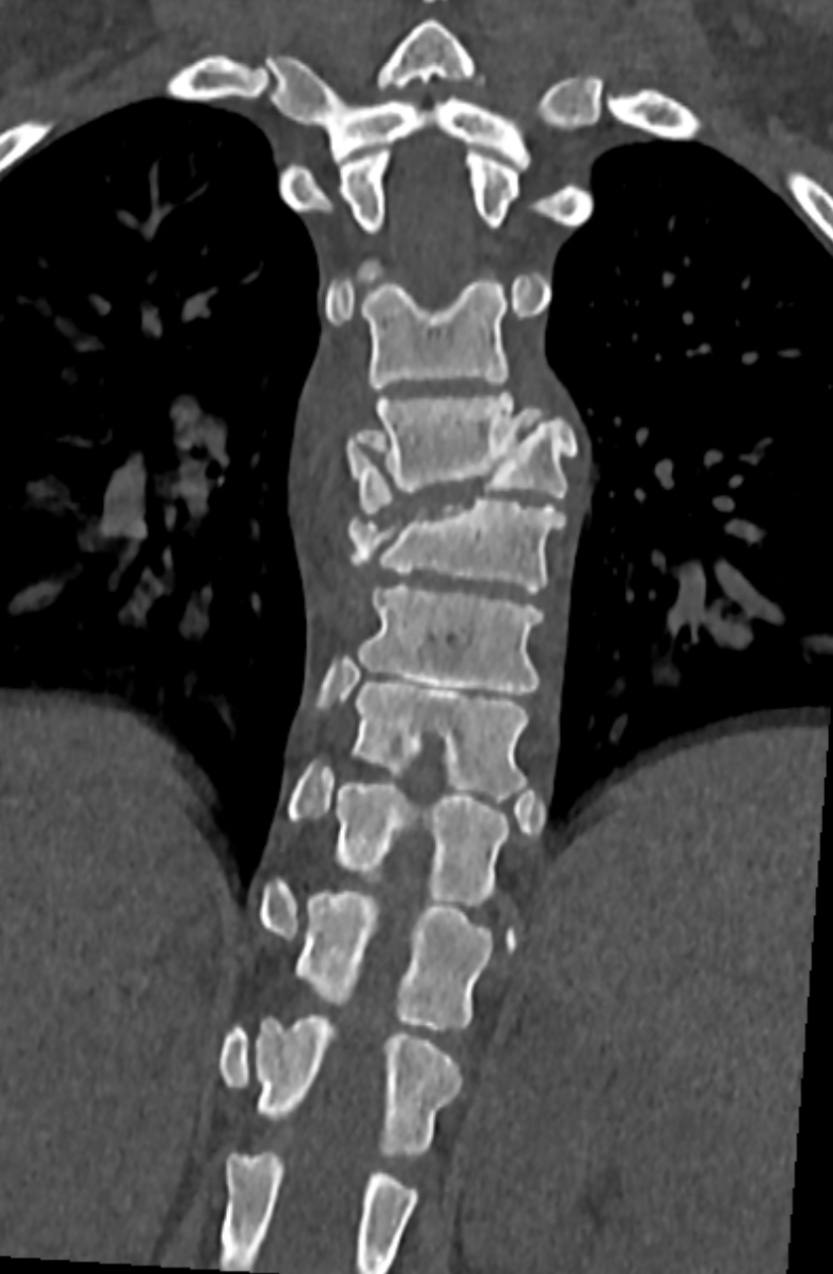

После стабилизации состояния и разрешения инфекционных осложнений девочку перевели в Новосибирский НИИТО для операции на позвоночнике. Хирурги столкнулись со сложнейшим случаем спондилоптоза — смещением позвонка с разрушением.

Операция длилась около 9 часов. Спинальные хирурги провели корригирующую вертебротомию — удалили часть поврежденного позвонка, исправили деформацию и зафиксировали позвоночник специальной металлоконструкцией. Во время операции врачи обнаружили, что дуральный мешок цел и пульсирует, что дает надежду на восстановление неврологических функций.